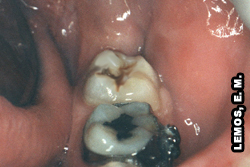

Caso clínico no. 02 - Idade 23 anos, sexo masculino, relato clínico: relata dor intermitente no 2o. molar inferior esquerdo, principalmente quando ingere líquidos gelados, porém a dor cessa alguns minutos após a remoção do estímulo.

Relata que a dor iniciou há cerca de 2 dias e as vezes dói sozinho, sem estímulo.

As vezes parece que a dor torna-se difusa e irradiada nos dentes inferiores posteriores esquerdo.

Na última noite o analgésico não foi muito efetivo como anteriormente.

Aspecto clínico do 2o. molar inferior com cárie na oclusal   RX 35, 36 e 37